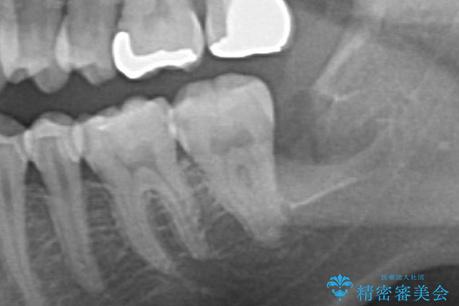

- 親知らずを抜きたいとのことで来院。

パノラマ写真(二次元的な写真)だと、下歯槽神経が近いかどうかわからないので

CT(三次元)を撮り、神経が近くないことを確認して抜歯を行いました。